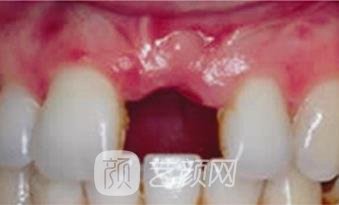

二、苏州相城口腔医院种植牙案例

怀着忐忑的心情来到了医院,让医生帮我看了看牙齿的问题,医生建议我将龋坏的牙齿拔掉,重新做个种植,我也听从了医生的专业意见,很快医生就帮我安排了手术,种植牙齿的过程中没有出现任何不良的情况,手术很顺利的就做完了,做完手术之后开始不太适应,经过了一段时间的磨合,牙齿用着就顺利多了,跟我自己的牙没太大区别,正常的咬合和咀嚼功能都挺好的。